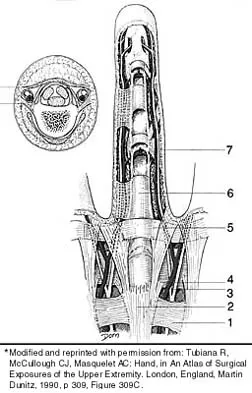

Which of the following structures runs through the site indicated by the arrow in Figure 11?

Explanation

Which of the following anatomic structures is labeled 6 in Figure 27?

Explanation